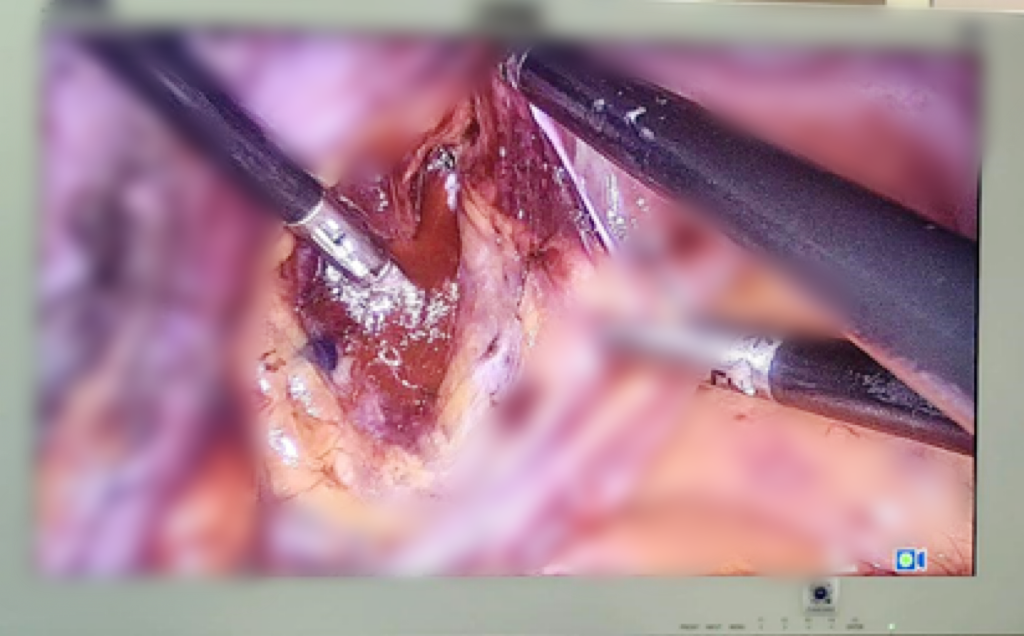

患者入院后,魏力主任微创团队通过对患者病情的充分评估,为其制定了精准微创手术的治疗方案:子宫内膜癌分期手术(腹腔镜下全子宫+双侧附件切除术+前哨淋巴结活检术)。该手术特点是具有提高诊断的准确性,减少手术范围,降低手术并发症等优势,术后第二天就能下床活动,术后4、5天就能出院。

大部分妇科恶性肿瘤是通过淋巴转移的,所以手术是需要切除盆腔淋巴结以明确有无淋巴结转移,并截断其转移途径,但是对于恶性肿瘤系统的淋巴结清扫术,术后出现相关并发症淋巴囊肿、淋巴水肿、乳糜瘘、血管损伤、神经损伤等会影响患者的生活质量,所以腹腔镜下前哨淋巴结活检能通过微创的方式,精准、有效的评估患者病情。

前哨淋巴结是肿瘤转移的第一站。前哨淋巴结阳性可作为区域淋巴结转移的标志。通俗的讲前哨淋巴结就像淋巴结中的哨兵发现敌情的前沿哨所,如果肿瘤发生扩散转移第一站最先到达的淋巴结就叫前哨淋巴结。术中采用示踪剂,将其注射于宫颈,然后在高清荧光腹腔镜下观察显影并手术,通过对前哨淋巴结的活检从而达到了解整个盆腔淋巴结的转移情况,避免系统性的淋巴结清扫,手术时间短,术后并发症少,子宫内膜癌I期患者前哨淋巴结预测淋巴结转移:阳性预测值为97.2%,阴性预测值为99.6%。